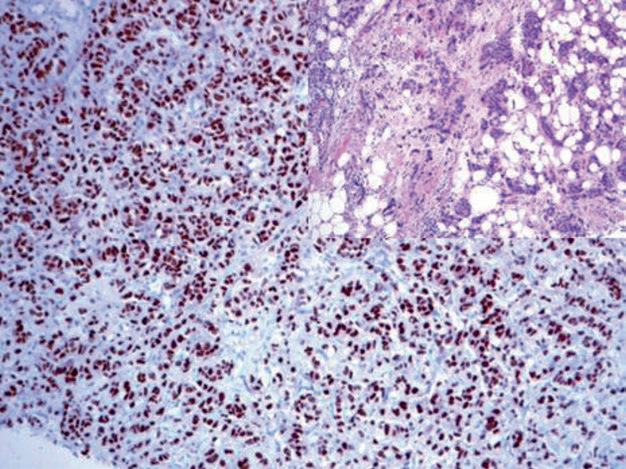

GATA-3 is involved in the regulation of breast luminal epithelial proliferation and differentiation, as well as in the differentiation of T lymphocytes and skin appendages. In clinical practice, GATA-3 is widely used in the diagnosis and differential diagnosis of primary and metastatic breast cancer and transitional cell carcinoma. Up to 90% of breast cancers express GATA-3, but the positivity rate is lowest in triple-negative breast cancer, and also low in metaplastic breast cancer and sarcomatoid breast cancer. In male breast cancer, the GATA-3 positivity rate is only one-third. Strong positive expression of GATA-3 in breast cancer is also accompanied by ER expression; high expression of GATA-3 generally indicates a better prognosis.

Figure 3. Breast invasive ductal carcinoma, bone metastasis; immunohistochemistry shows strong positive nuclear expression of GATA-3 in tumor cells.

As mentioned earlier, GATA-3 can also be applied to the diagnosis and differential diagnosis of primary and metastatic transitional cell carcinoma, which will be detailed later in this series of articles. However, besides these, many other tissues and tumors express GATA-3, and caution should be exercised in interpretation to avoid pitfalls. Specifically, mesothelioma, squamous cell carcinomas of various organs, pancreatic ductal adenocarcinoma, skin appendage tumors, and various benign and malignant salivary gland tumors (such as salivary duct carcinoma, acinic cell carcinoma, adenoid cystic carcinoma, epithelial-myoepithelial carcinoma) show varying degrees of GATA-3 expression. It has also been reported that a few endometrial cancers express GATA-3. GATA-3 expression is also characteristic of T lymphocytes and peripheral T-cell lymphoma. Notably, reactive mesothelium also expresses GATA-3. Due to these issues, the specificity of GATA-3 should be considered when used for breast tumor and urothelial tumor diagnosis.